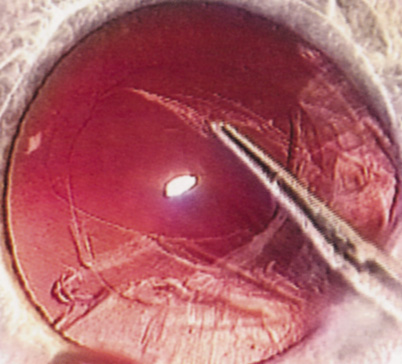

POSTERIOR POLAR CATARACTS

Another huge step forward was taken in the early 1980s when French surgeon Danielle Aron-Rosa and her colleagues introduced the neodymium:yttrium-aluminum-garnet (Nd:YAG) laser for performing posterior capsulotomy, which eliminated an additional procedure in the operating room.13 Clifford Terry introduced the surgical keratotomer, which provided us with a new understanding of astigmatism,14 leading to the combination of astigmatic keratotomy with phacoemulsification to reduce pre-existing astigmatism introduced by Robert Osher in 1983.15,16 Then in 1985, Thomas Mazzocco developed and implanted the first foldable IOL17; Australian Graham Barrett and associates ushered us into the materials era with the use of silicone, hydrogels, and acrylics.18 Remarkable insights by David Apple correlated clinical observation with histopathology using the photographic technique developed by Kensaku Miyake of Japan.19